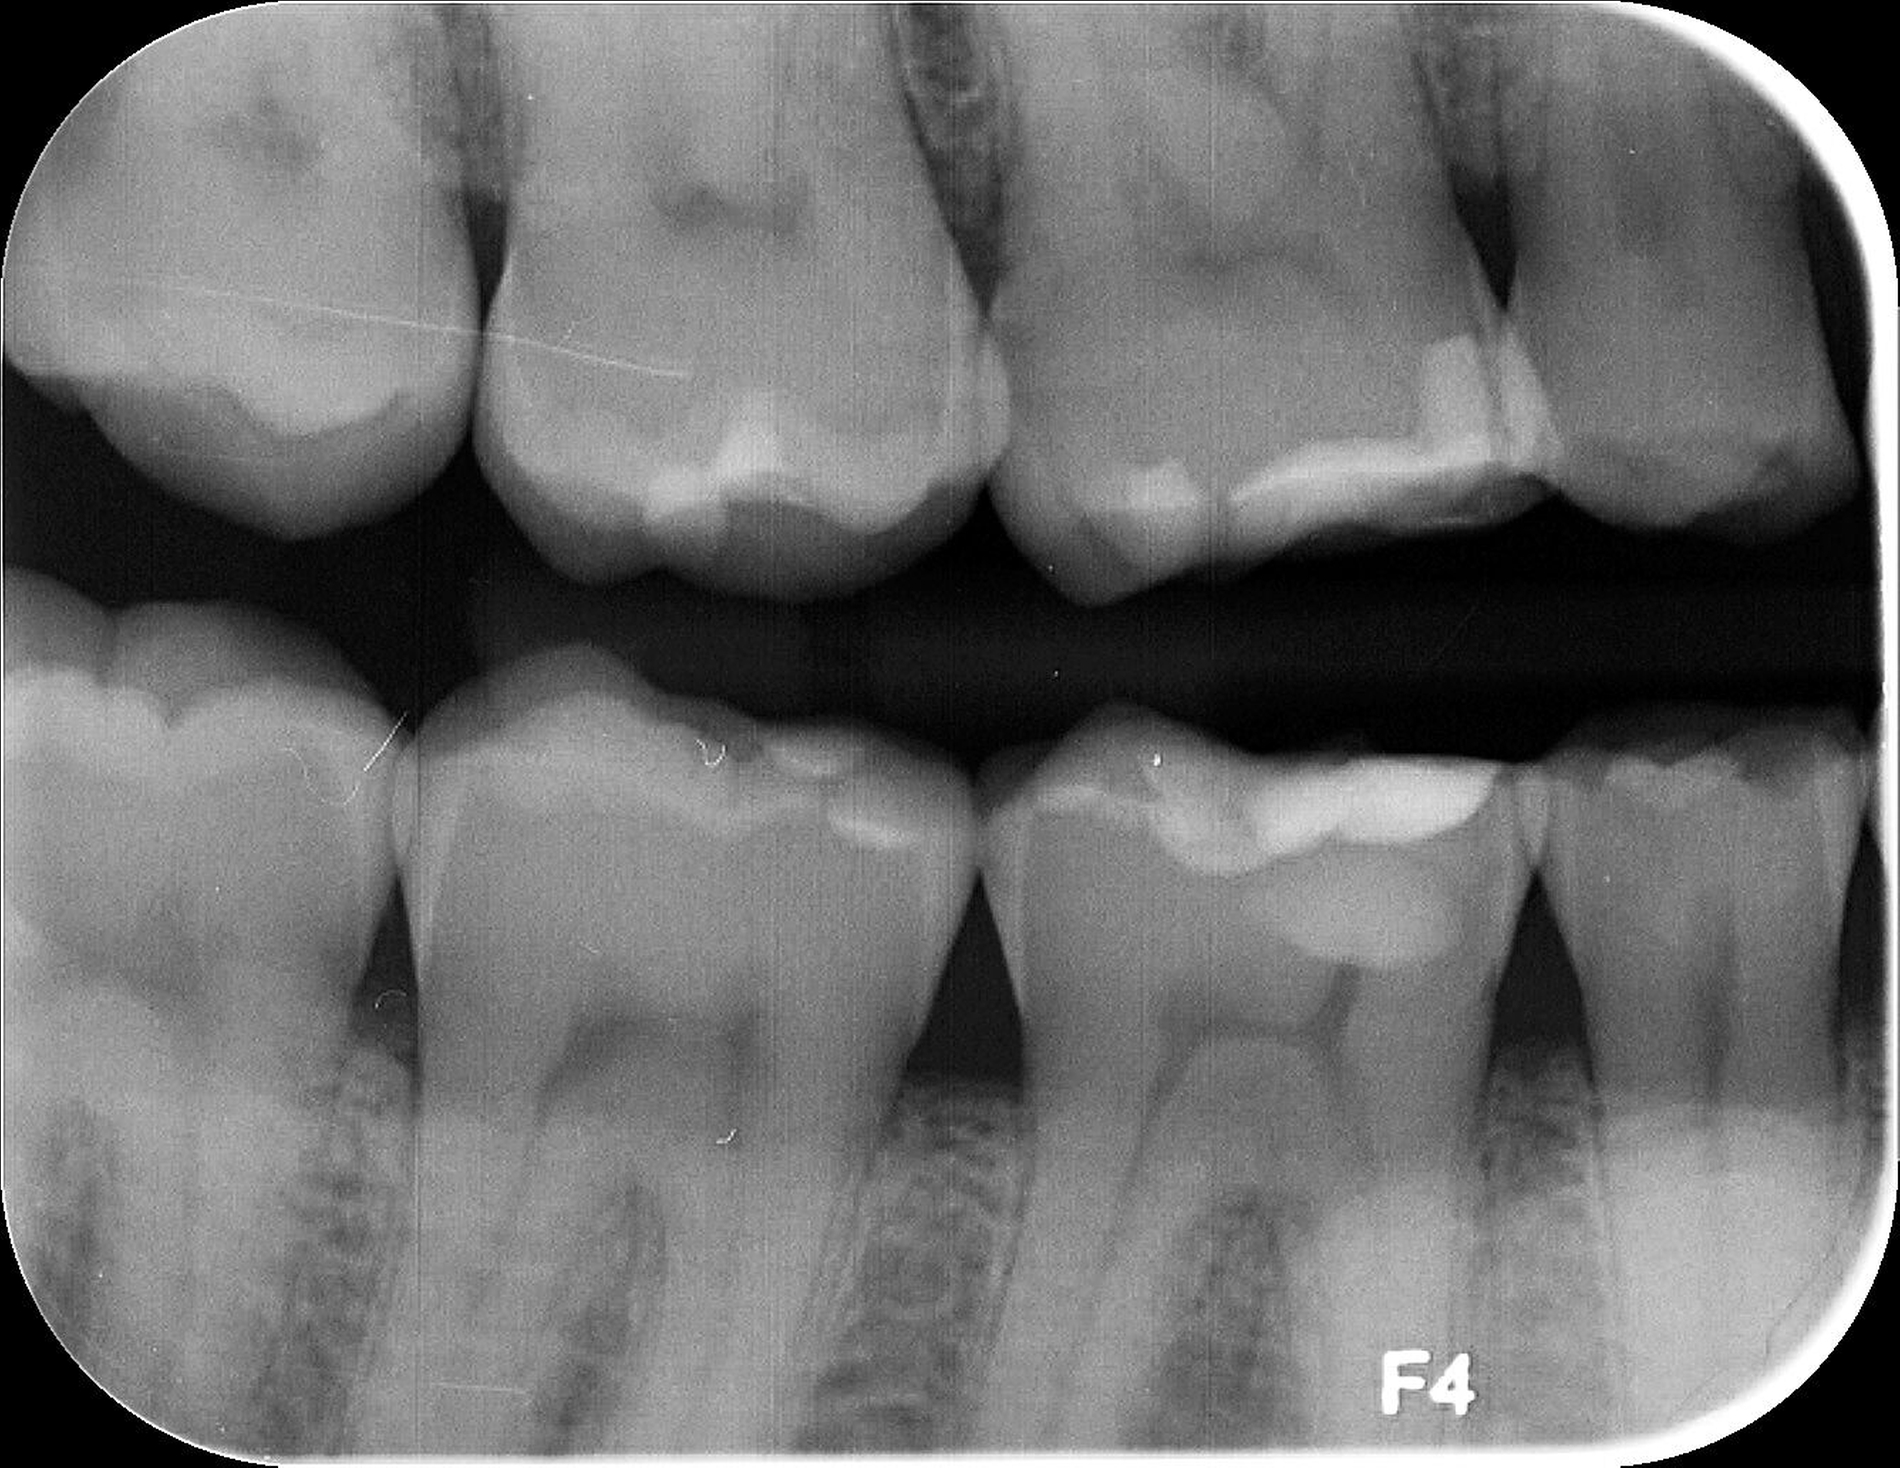

Das unter Beteiligung des Autors entwickelte Tooth Wear Evaluation System (TWES) 2.0 [Wetselaar et al., 2020] identifiziert per Screening Patienten mit erhöhten Verschleißwerten, vergleichbar mit dem PSI in der Parodontologie oder dem CMD-Kurzbefund. Bei auffälligen Werten folgt ein differenzierter Zahnverschleiß-Status einschließlich der Erfassung oraler und vestibulärer Substanzverluste [Wetselaar et al., 2016 sowie von Pathologie-Symptomen und einer strukturierten Diagnose [Tonetti und Sanz, 2019; Wetselaar, 2020]. Den Einsatz in der Praxis illustriert der in den Abbildungen beschriebene Patientenfall aus dem CMD-Centrum Hamburg-Eppendorf.

Im Unterschied zum Zahnverschleiß-Screening wertet der Zahnverschleiß-Status den höchsten Verschleißgrad pro Zahn aus, und zwar okklusal/inzisal, oral und vestibulär (Abbildungen 4b und 4c, Tabelle 1). Wichtig für die Planung therapeutischer Maßnahmen ist die Frage, welche Zähne okklusal in Kontakt stehen, denn die Behandlung von Zähnen mit erheblichem Zahnverschleiß lässt keinen weiteren Substanzverlust zu und erfordert bei Zähnen in Kontakt absehbar eine Erhöhung der vertikalen Dimension der Okklusion.

Im Beispiel ist daher die Diagnose ein generalisierter erheblicher und lokalisierter moderater pathologischer Zahnverschleiß überwiegend mechanischer und zudem chemischer Ursache. Die sich daraus ableitende Erkenntnis ist, dass in allen Sextanten Zähne freiliegende Dentinkerne aufweisen (generalisierter moderater Zahnverschleiß), dass darüber hinaus Zähne erheblich geschädigt und somit gefährdet sind, dass Merkmale eines pathologischen Geschehens bestehen – und dass als Ursache neben dem dominierenden Bruxismus ein Säureeinfluss hinzukommt.

Auch wenn Restaurationen nach Möglichkeit vermieden werden sollten, ist deren Verfügbarkeit für die Betroffenen individuell höchst wichtig, weil sie bestehende Schmerzen beseitigt, die verlorengegangene Kauleistung wiederherstellt und ästhetische und nicht zuletzt auch phonetische Einschränkungen aufhebt. Bei dem in den Abbildungen beschriebenen Fall korrelierte der erhebliche Zahnverschleiß mit der Lokalisation der Zahnschmerzen des Patienten. Direkte Restaurationen mit Kompositen hatten keinen Bestand. Die durchgeführte restaurative Behandlung hingegen hat Bestand, die Schmerzen waren danach umgehend verschwunden und sind seit zehn Jahren nicht wiedergekehrt.

Dabei führt die Verfügbarkeit hochfester Dentalkeramiken heute zu viel weniger invasiven Restaurationen als früher durchgängig übliche metallkeramische Kronen, und die Transluzenz der keramischen Werkstoffe ermöglicht zudem natürlichere Restaurationen. Der beschriebene Behandlungsfall zeigt, wie eine mehrstufige Zahnverschleiß-Diagnostik im Praxisalltag umgesetzt wird, mit initialem Zahnverschleiß-Screening und einer im Bedarfsfall erfolgenden erweiterten Diagnostik per Zahnverschleiß-Status.